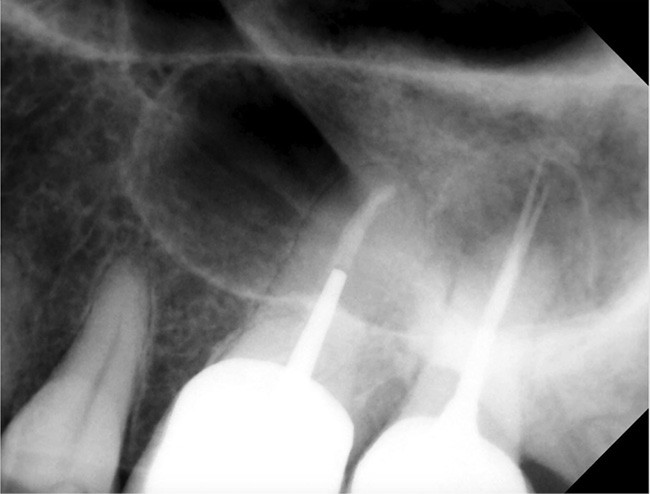

Chirurgie endodontique

L’Er:YAG a également sa place en chirurgie endodontique. En mode ablatif, il permettra l’élimination des tissus de granulation et des tissus fibro-kystiques en assurant la stérilisation de la crypte osseuse ainsi formée.

La résection apicale et la préparation a retro exposent des canaux et des tubulis dentinaires infectés, qui pourront là aussi, être décontaminés par l’action du laser Er:YAG et de l’eau distillée [36].

Les espaces non accessibles à l’instrumentation conventionnelle pourront, là aussi, être débridés et stérilisés (fig. 11a à f). Cette procédure semble accélérer de manière très significative les processus de régénération osseuse (fig. 11f).